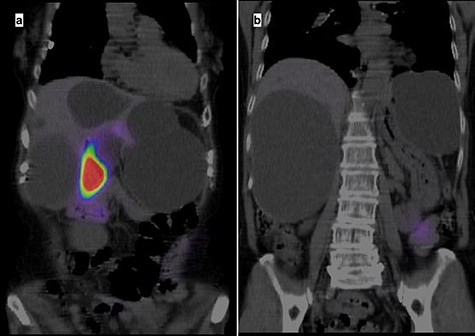

A 74-year-old woman presented with right upper abdominal pain and poor dietary intake. She had no notable medical history or history of abdominal trauma. Abdominal computed tomography (CT) showed multiple liver cysts, with the size of the largest cyst in the right lobe measuring 155 × 113 × 106 mm (Fig. 1a). In addition, a large cyst measuring 135 mm in the left lateral lobe strongly compressed the stomach (Fig. 1b). T1-weighted magnetic resonance imaging revealed different findings in the right and left lobe cysts, and there were no enhanced structures in the liver cysts (Fig. 2). Positron emission tomography-CT did not show increased 18F-fluorodeoxyglucose metabolism in any of the liver cysts (Fig. 3). Moreover, hepatobiliary scintigraphy with CT showed no biliary communication with the liver cysts (Fig. 4). The patient was diagnosed with symptomatic and multiple liver cysts with no biliary communication or malignancy. Therefore, LF was performed.

Hepatobiliary scintigraphy with CT highlighting only the gallbladder, with no biliary communication with the liver cysts.